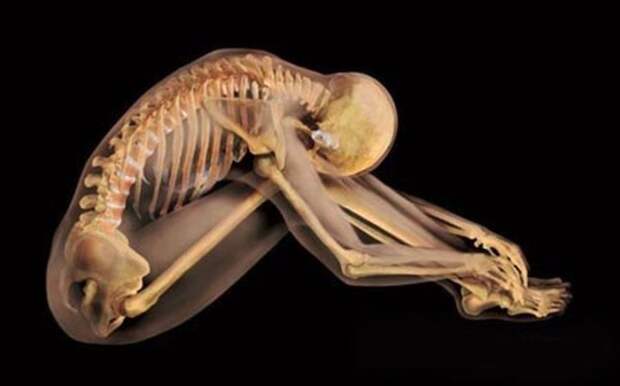

Естественная красота изгибов